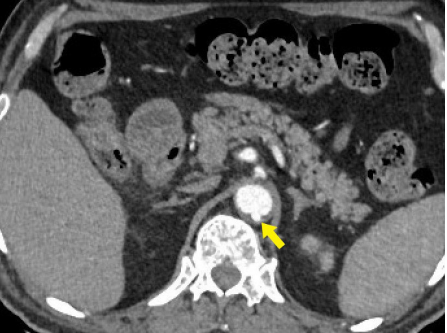

Figure 4 Axial CT angiography image in the arterial phase shows an aortic dissection of the descending aorta with a small-sized true lumen (yellow arrow) and a larger false lumen (red arrow). The true lumen shows more enhancement as compared to the false lumen.

Contrast-enhanced CT angiography (CTA) findings of AD include the presence of an intimal flap separating the true lumen from the false lumen, present in approximately 70% of AD cases (Figure 5a). Identification of true lumen is essential to the diagnosis of AD, for proper planning of endovascular intervention (Table 2). Features in support of true lumen are a smaller size than false lumen, calcifications along its outer wall or intimal flap, contiguity with unaffected aortic lumen, more enhancement as compared to the false lumen (Figure 4) (Figure 8a, 8b). Features in support of false lumen are larger lumen size than true lumen, non-communication with the unaffected aorta, less enhancement as compared to the true lumen, “cobweb sign” and “beak sign”.6,17,21 “Cobweb sign” was described by Williams et al as “residual ribbons of media that have incompletely sheared from the aortic wall during the dissection process” 22 They are seen as thin, linear filling defects of low attenuation within the false lumen (Figure 5a). “Beak sign” was described by Le Page et al as “the cross-sectional imaging manifestation of the wedge of hematoma that cleaves a space for the propagating false lumen” (Figure 6) (Figure 9).23 Occasionally, a circumferential flap may form because of dissection involving the entire aortic intima & subsequent intimointimal intussusception. The true lumen takes a fusiform or a cylindrical shape and gives a “windsock appearance” (Figure 5b).17